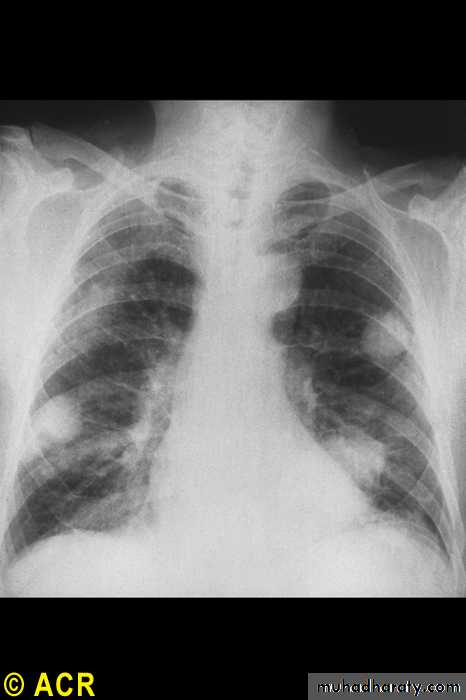

Rheumatoid arthritis: pulmonary nodules

40

Pulmonary

NodulesPleural effusions

Fibrosing alveolitis

Bronchiolitis

Caplan's syndrome